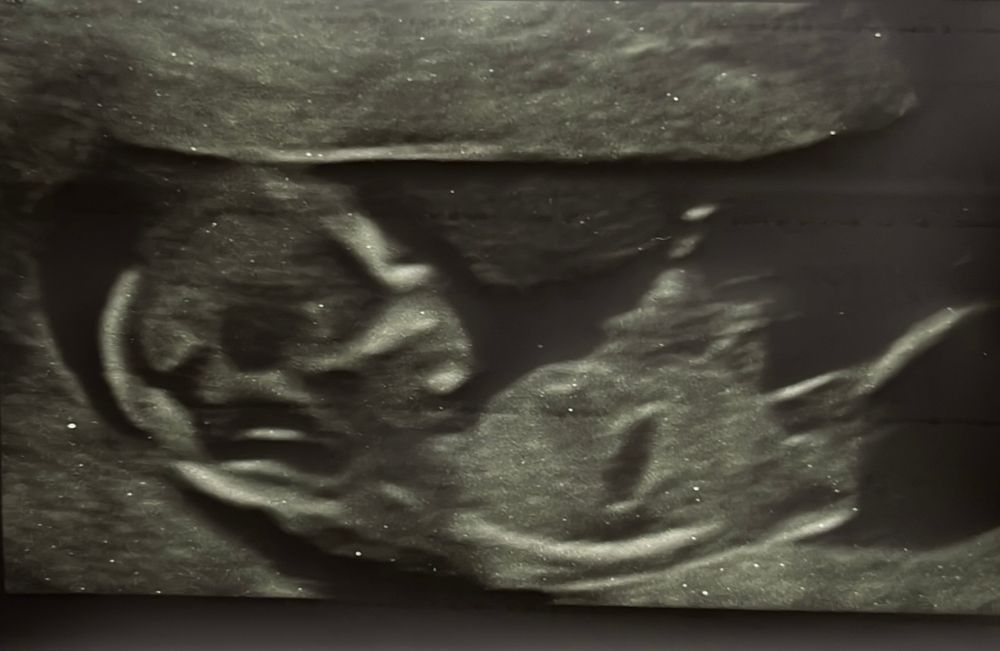

Нателла, может, это бугорок )) Изображение

Буду мамой дочки , может, ну либо палец от руки🙈

Нателла, 🙈😂